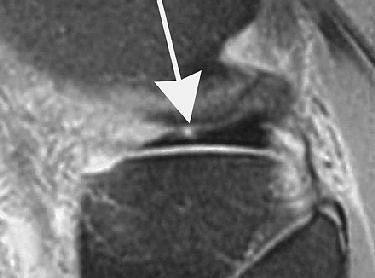

![]() |

| Marching cleft sign in discoid lateral meniscus indicates radial meniscal tear in 21-year-old man. Conventional sagittal proton density images (2,000/20) with fat saturation show vertical high signal (arrows) extending through adjacent two body segments, indicating cleft marching centrally and anteriorly indicating radial tear. |